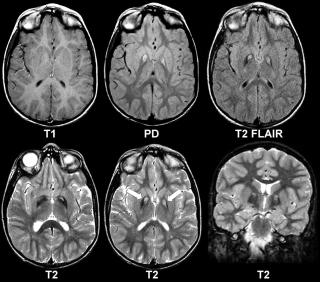

о Вследствие небольшого размера пучков и косого их хода рекомендуется выполнять томографию с толщиной среза 3 мм

о В поле зрения должна входить область от большеберцово-таранного сустава до предплюсне-плюсневых суставов:

- Позволяет обнаружить часто встречающиеся сопутствующие патологические изменения

о Чувствительные к жидкости последовательности, аксиальная и коронарная плоскости

о Для оценки анатомии-Т1 ВИ и ППВИ в сагиттальной и коронарной плоскостях